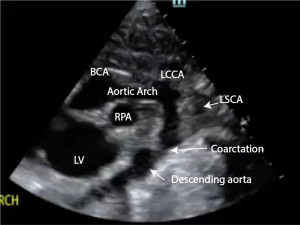

Ultrasound

Echocardiography is usually the initial modality used for identification and evaluation of cardiac myxomas. They appear as hyperechogenic lesions with a well-defined stalk. Moreover, echocardiography can be useful to assess the mobility of the tumor, as it often protrudes through valve flaps.